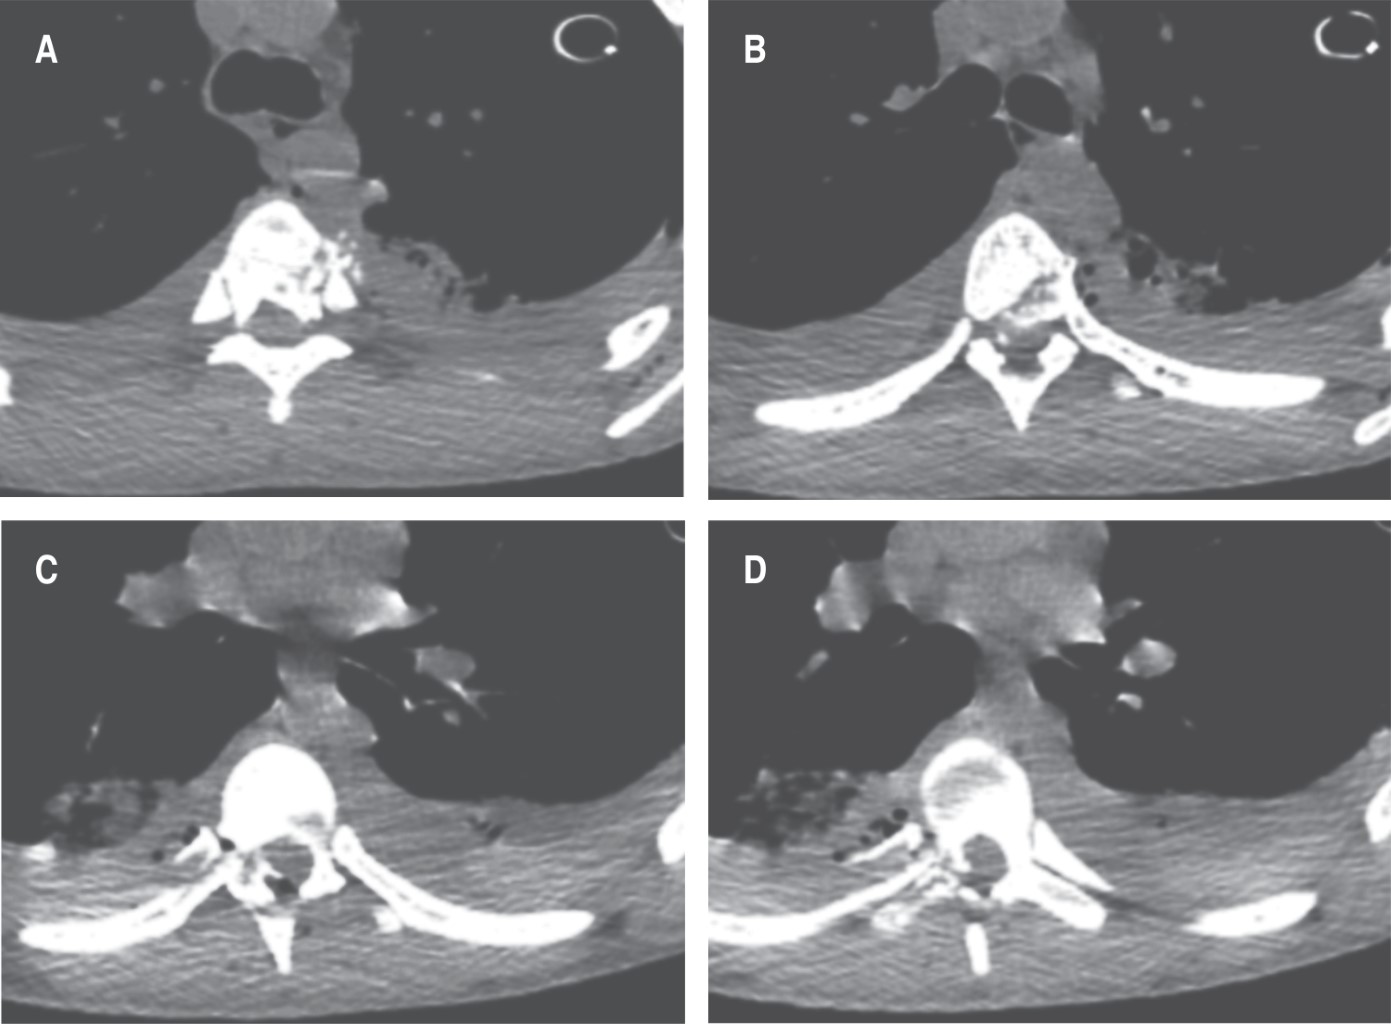

Se interconsulta al servicio de cirugía de columna, quien concluye en los siguientes diagnósticos a partir de exploración y hallazgos tomográficos (Figuras 1 y 2): fractura por estallido de T5 y T6 Gustillo-Anderson IIIA, fractura de los pedículos derechos de T6 y T7, traumatismo raquimedular secundario a proyectil por arma de fuego Frankel A, ASIA A y fractura de articulación costovertebrales de arcos costales 8 y 9; por lo que a los 11 días de estancia intrahospitalaria se procedió a instrumentación torácica posterior con hemilaminectomía para descompresión, estabilización y movilización, con pronóstico malo para la función. Durante la intervención se observa lesión del pedículo y lámina T5, por lo que no es posible instrumentar dicho nivel, optando por instrumentar dos niveles por encima y dos niveles por debajo. Se realizó colocación de tornillos transpediculares poliaxiales en T3, T4, T6 y T7 con colocación de 30 cc de injerto óseo en chips (Figura 3), asistido por fluoroscopia.